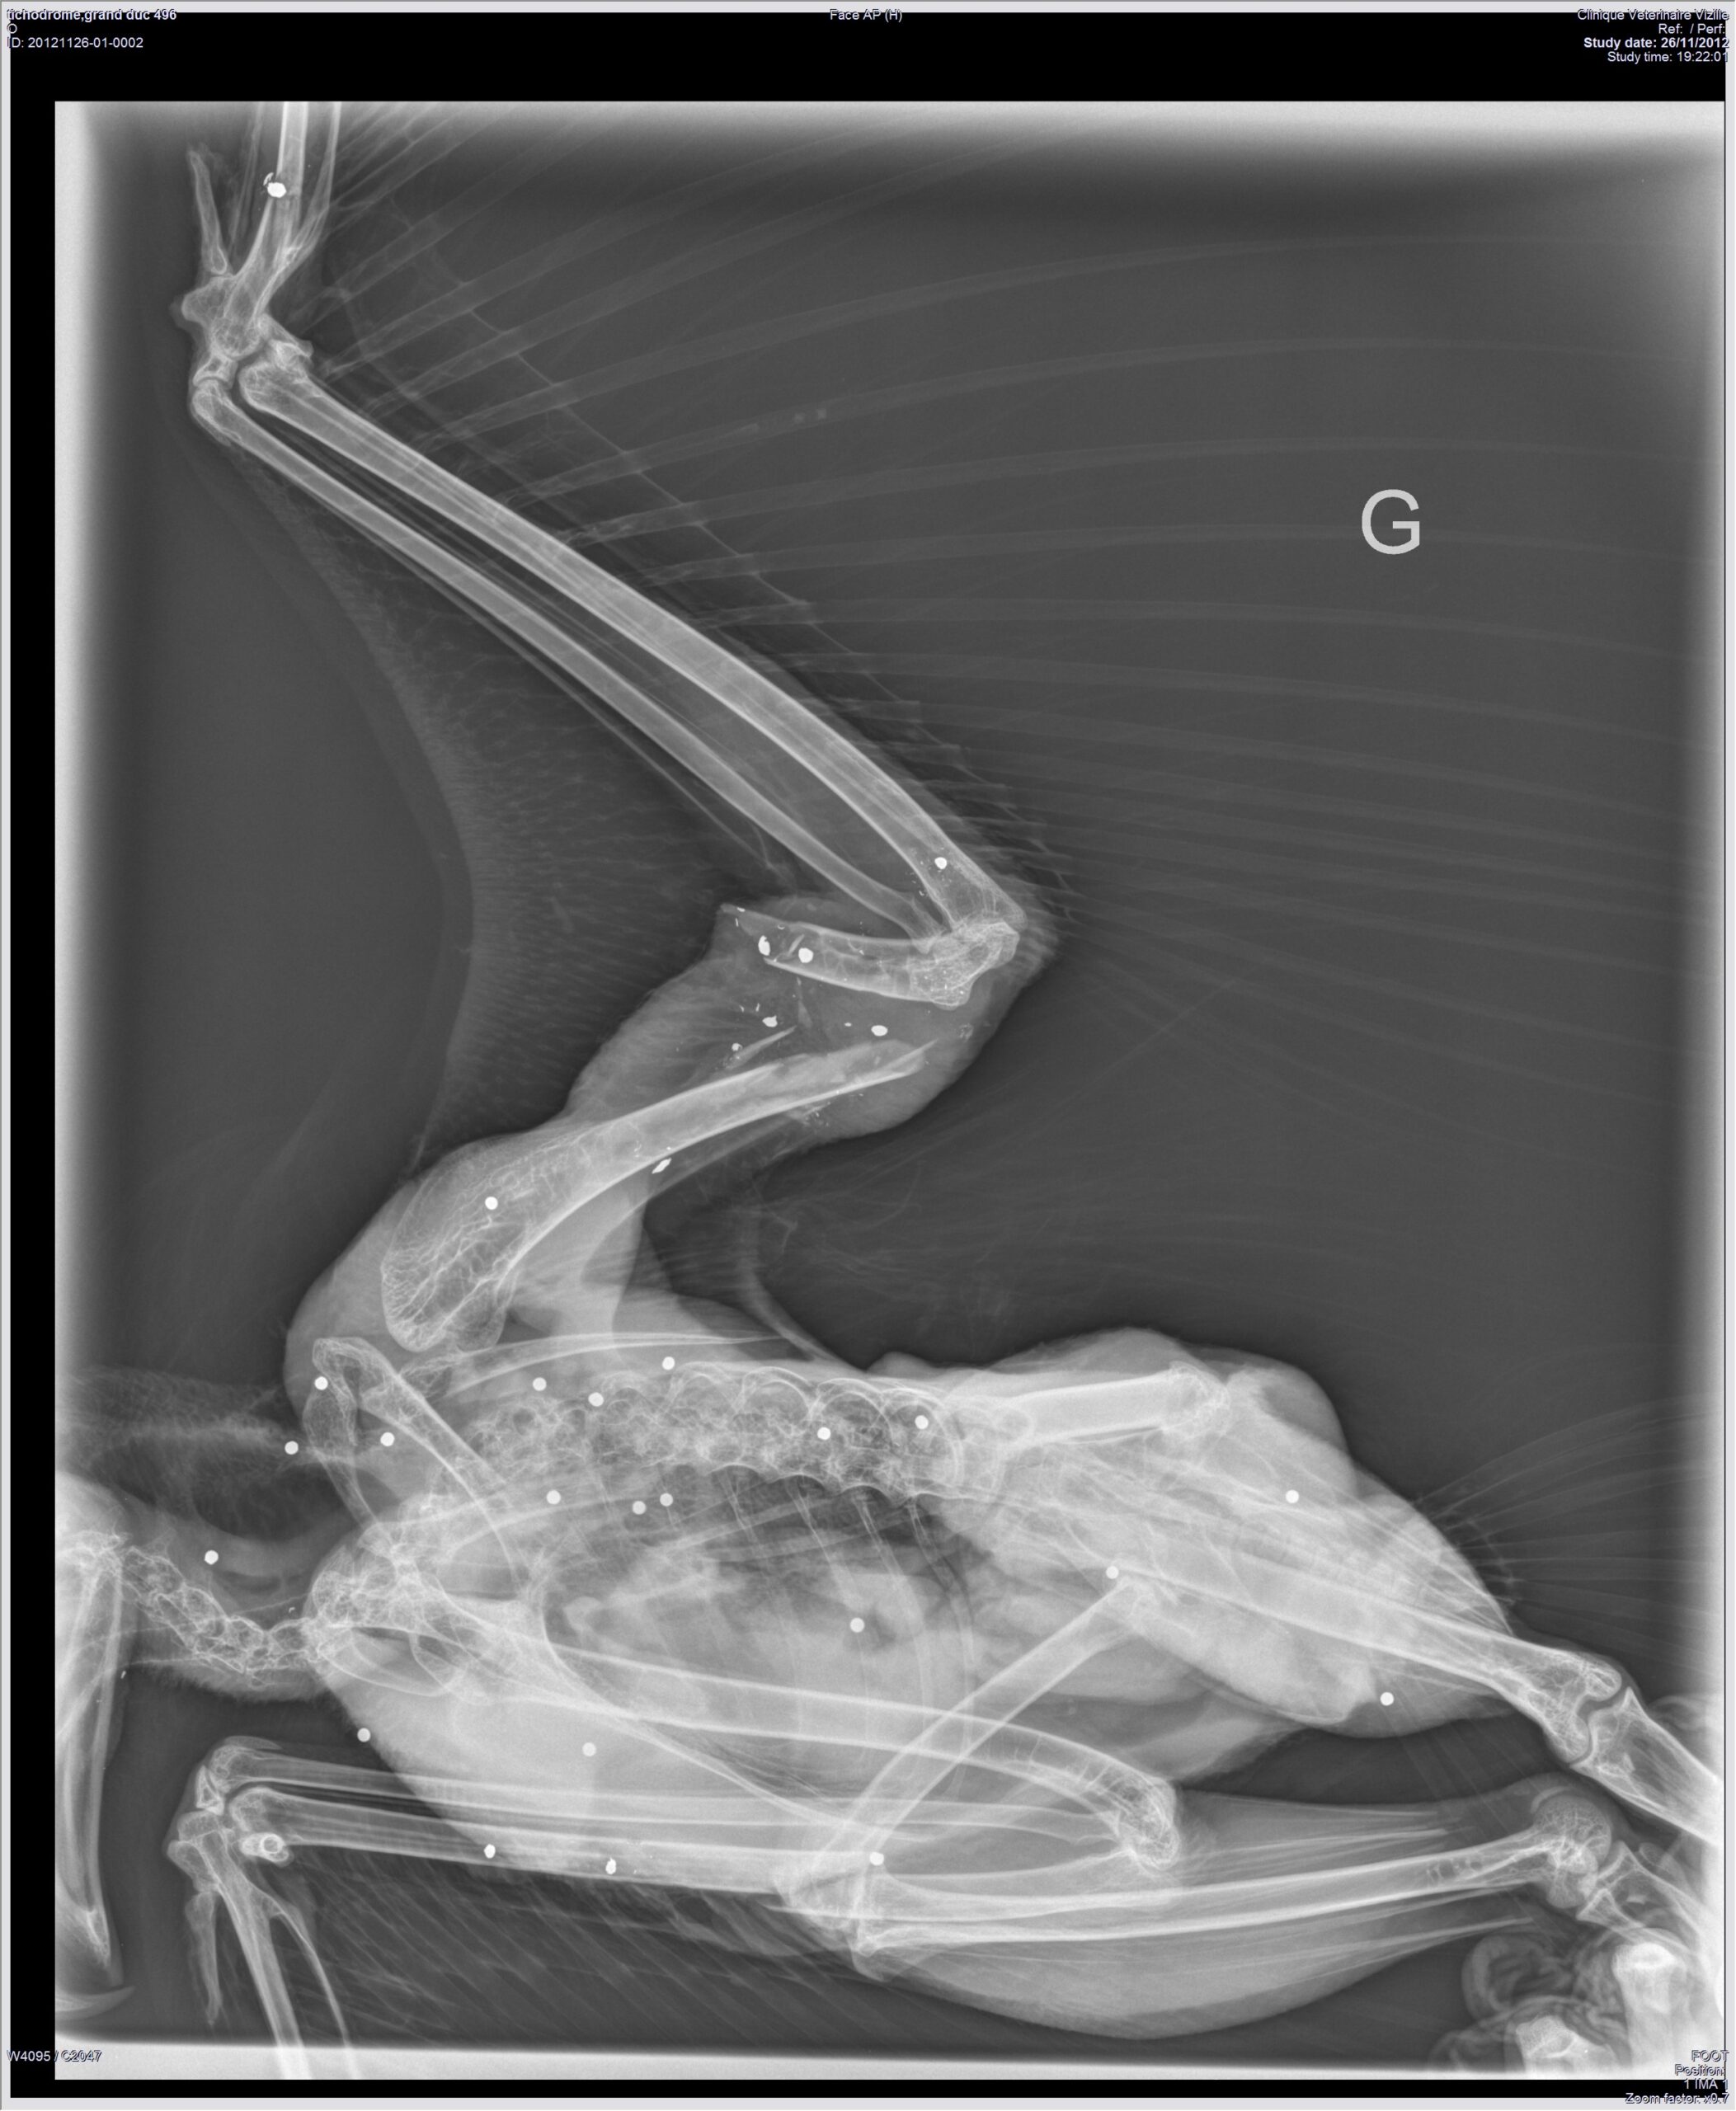

Deux Grands-ducs plombés en Isère

En novembre et décembre 2012, le Centre de soin le Tichodrome en Isère a reçu deux Grands-ducs plombés. Le premier, […]